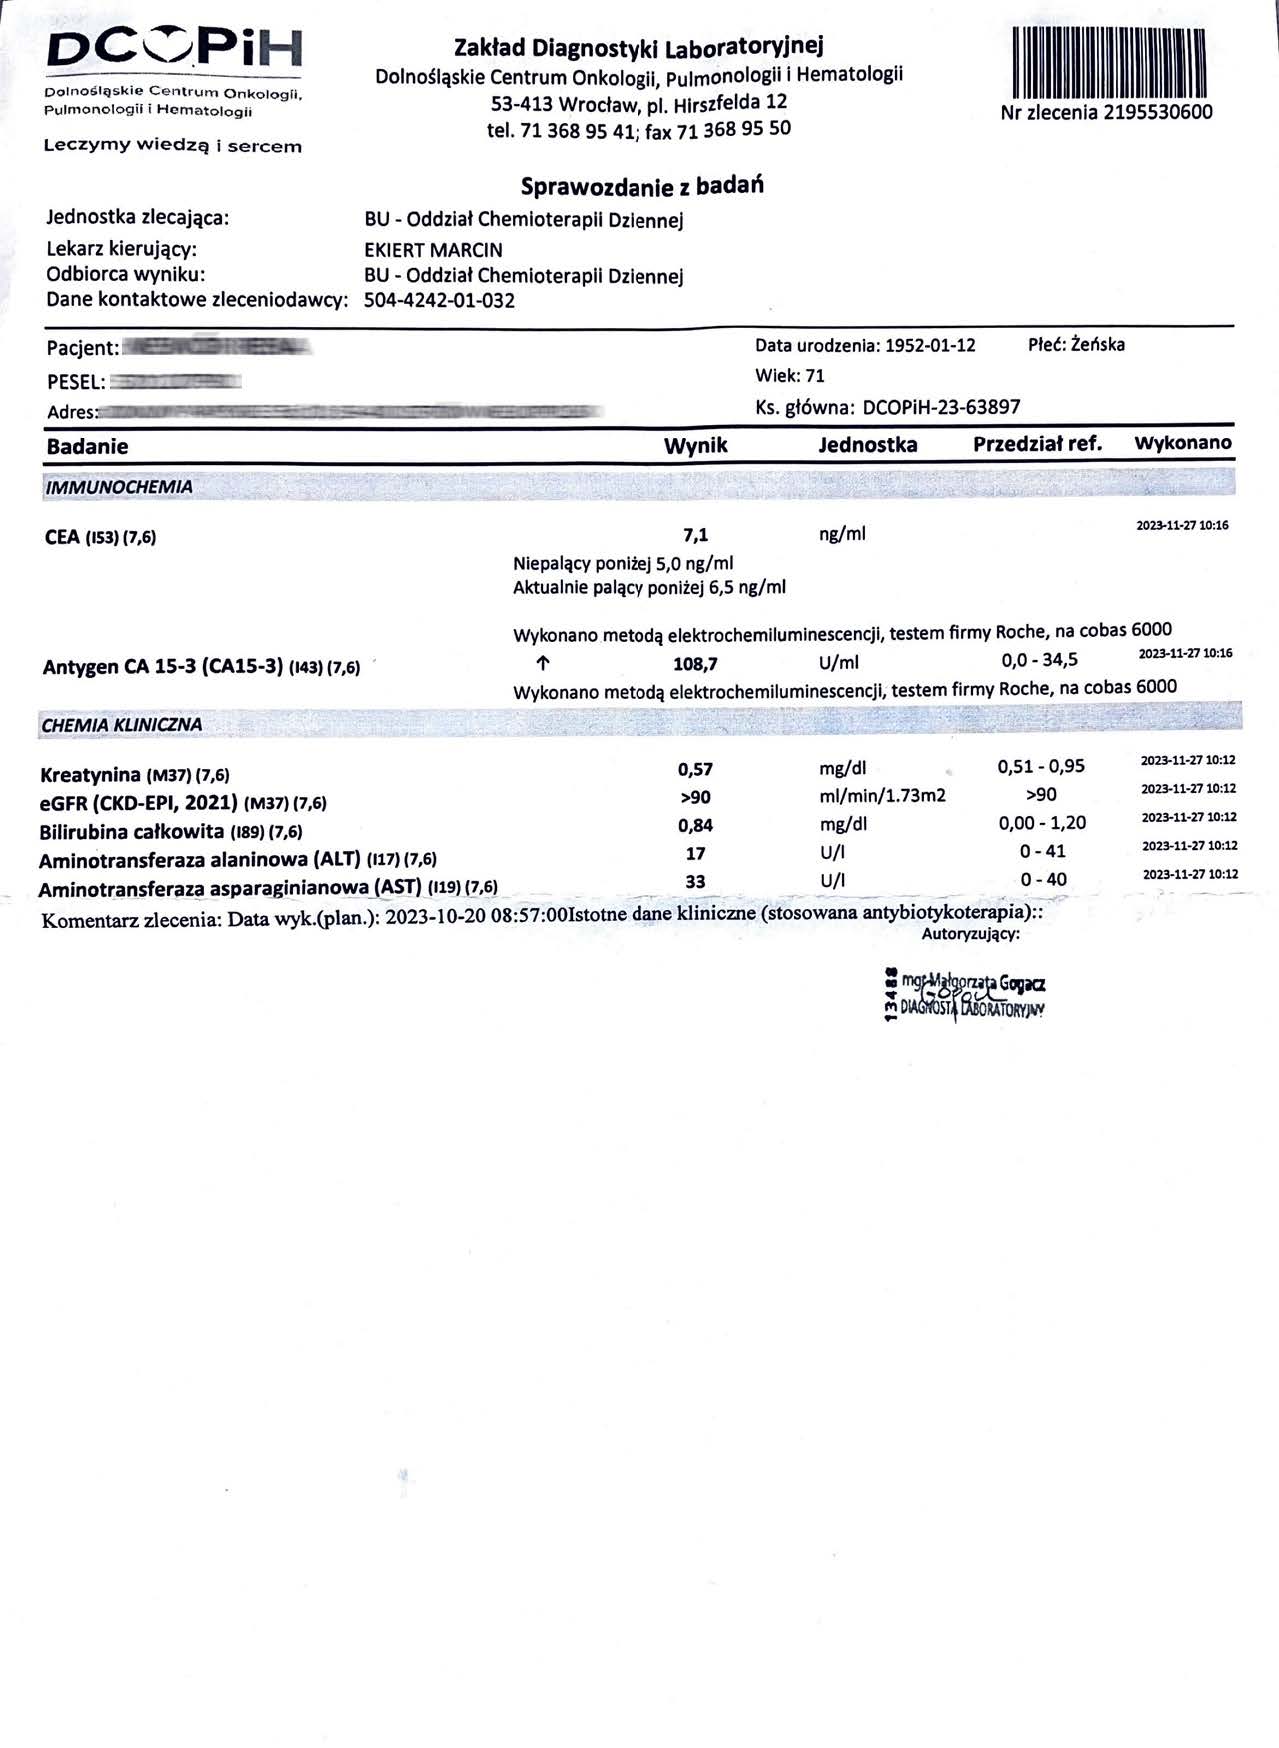

EFEKT PREPARATU NA RAKA PIERSI

Kobieta lat 71, rak piersi w IV stadium, zaawansowane stadium metastazy. W trakcie stosowania preparatu odnotowano spadek markerów Ca 15-3 z wartości 140,0 U/ml do 78,3 U/ml oraz spadek markeru CEA z 11,8 ng/ml do 8,4 ng/ml w zaledwie 3 miesiące, odnotowano stabilność szpiku. Wyniki wykazują zahamowanie progresji, dodatkowo odnotowano cechy uzupełniające terapię farmakologiczną, więc jest to jeden z przykładów wspomagania leczenia systemowego.